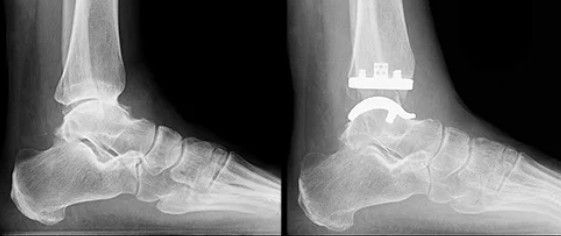

Prótese de Tornozelo (Artroplastia Total de Tornozelo):

- O que é: Envolve a substituição da articulação do tornozelo por componentes artificiais de metal e plástico, restaurando uma superfície lisa para o movimento.

- Indicação: É uma opção para pacientes com artrose avançada que desejam manter a mobilidade da articulação. A seleção do paciente é crucial, sendo indicada para aqueles com menor demanda física e sem grandes deformidades.

- Vantagens: Preserva o movimento do tornozelo, resultando em uma marcha mais natural e menos sobrecarga nas articulações adjacentes do pé.

- Desvantagens: Requer uma cirurgia complexa, e a prótese tem uma vida útil limitada, podendo precisar de revisão no futuro.